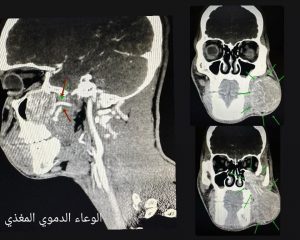

الخميس :6-2-2025:راجع مستشفى الحسين السلط الجديد أحد المواطنين لعيادة جراحة الوجه و الفكين وكان يشكو من انتفاخ متزايد في منطقة الخد وبعد اجراء الفحوصات الشعاعية و النسيجية ، تم تشخيص المريض بورم دموي حميد نادر، يسمى(juvenile nasopharyngeal angiofibroma)

عادة ما ينبع في البلعوم الانفي ، الا انه في هذه الحالة نابع من منطقة الحفرة تحت الصدغية في قاع الجمجمة (infratemporal fossa)، ممتد الى الخارج بجانب الفك السفلي الى منطقة الخد.

و بناءً على صور الاشعه، تم بفضل الله و كرمه عمل اجراء جراحي نوعي و معقد استمر لمدة ٨ ساعات و نصف، تم خلاله استئصال كامل للورم مع المحافظة الكاملة على الشرايين و الاعصاب الخامس و السابع ، و اغلاق الشريان المغذي للورم، دون حدوث أية مضاعفات تذكر، حيث تماثل المريض للشفاء و غادر غرفة العناية المشددة بصحة ممتازة.